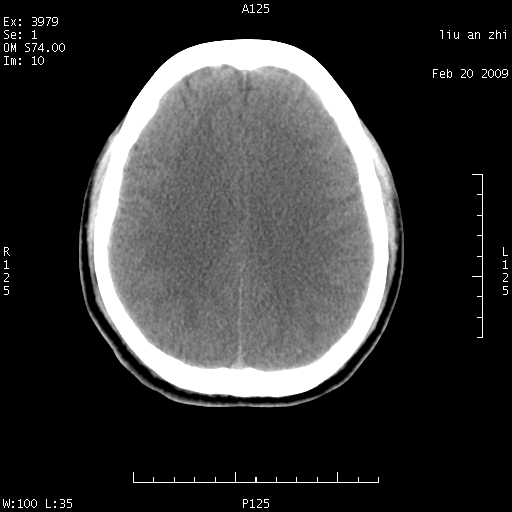

患者:男,32岁 被打伤后3天,自感头昏头痛作头颅ct检查。请大家看一下想什么??

请注意小脑幕!!!

ct18448的结果:mri检查左侧天幕下血肿